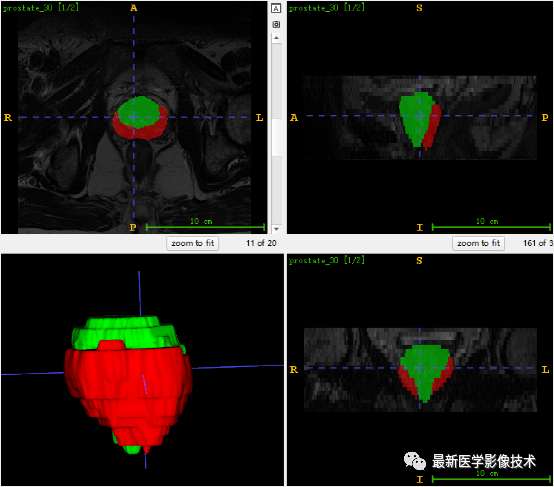

6、测试集分割结果